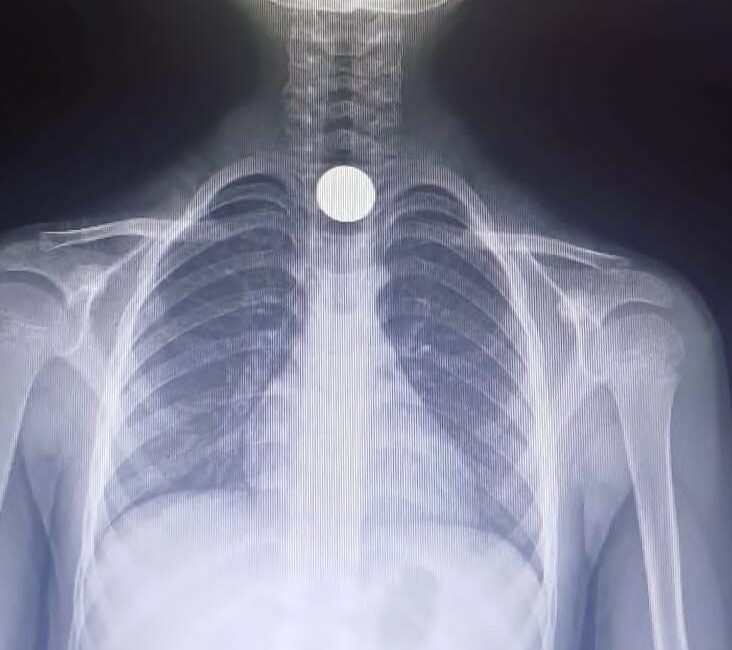

7 yaşındaki Ahmet Eymen U., yerde bulduğu 50 kuruşluk madeni parayı ağzına atıp yuttu. Olayı gören ailesi çocuğu özel araçla İnegöl Devlet Hastanesine götürdü. Acilde yapılan tetkiklerde paranın yemek borusunda kaldığı tespit edildi. Çocuk, boğazındaki paranın çıkarılması için Bursa Yüksek İhtisas Eğitim ve Araştırma hastanesine sevk edildi.